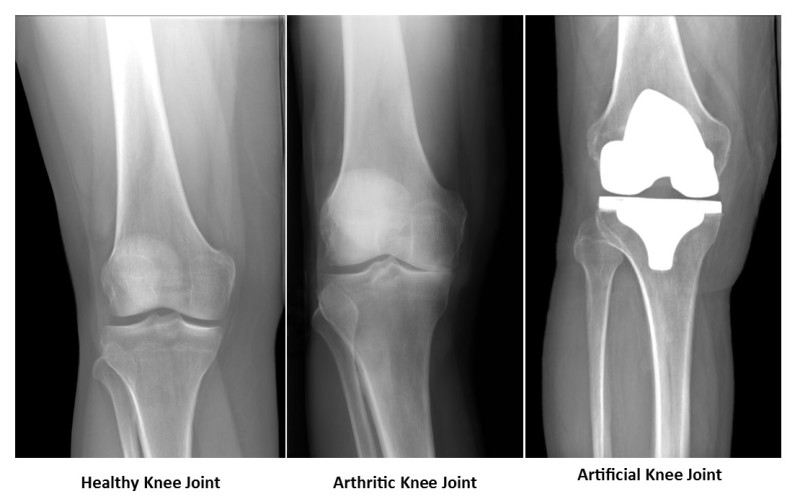

The knee is one of the largest and most complex joints in the body. The knee joins the thigh bone (femur) to the shin bone (tibia). The smaller bone that runs alongside the tibia (fibula) and the kneecap (patella) are the other bones that make the knee joint.